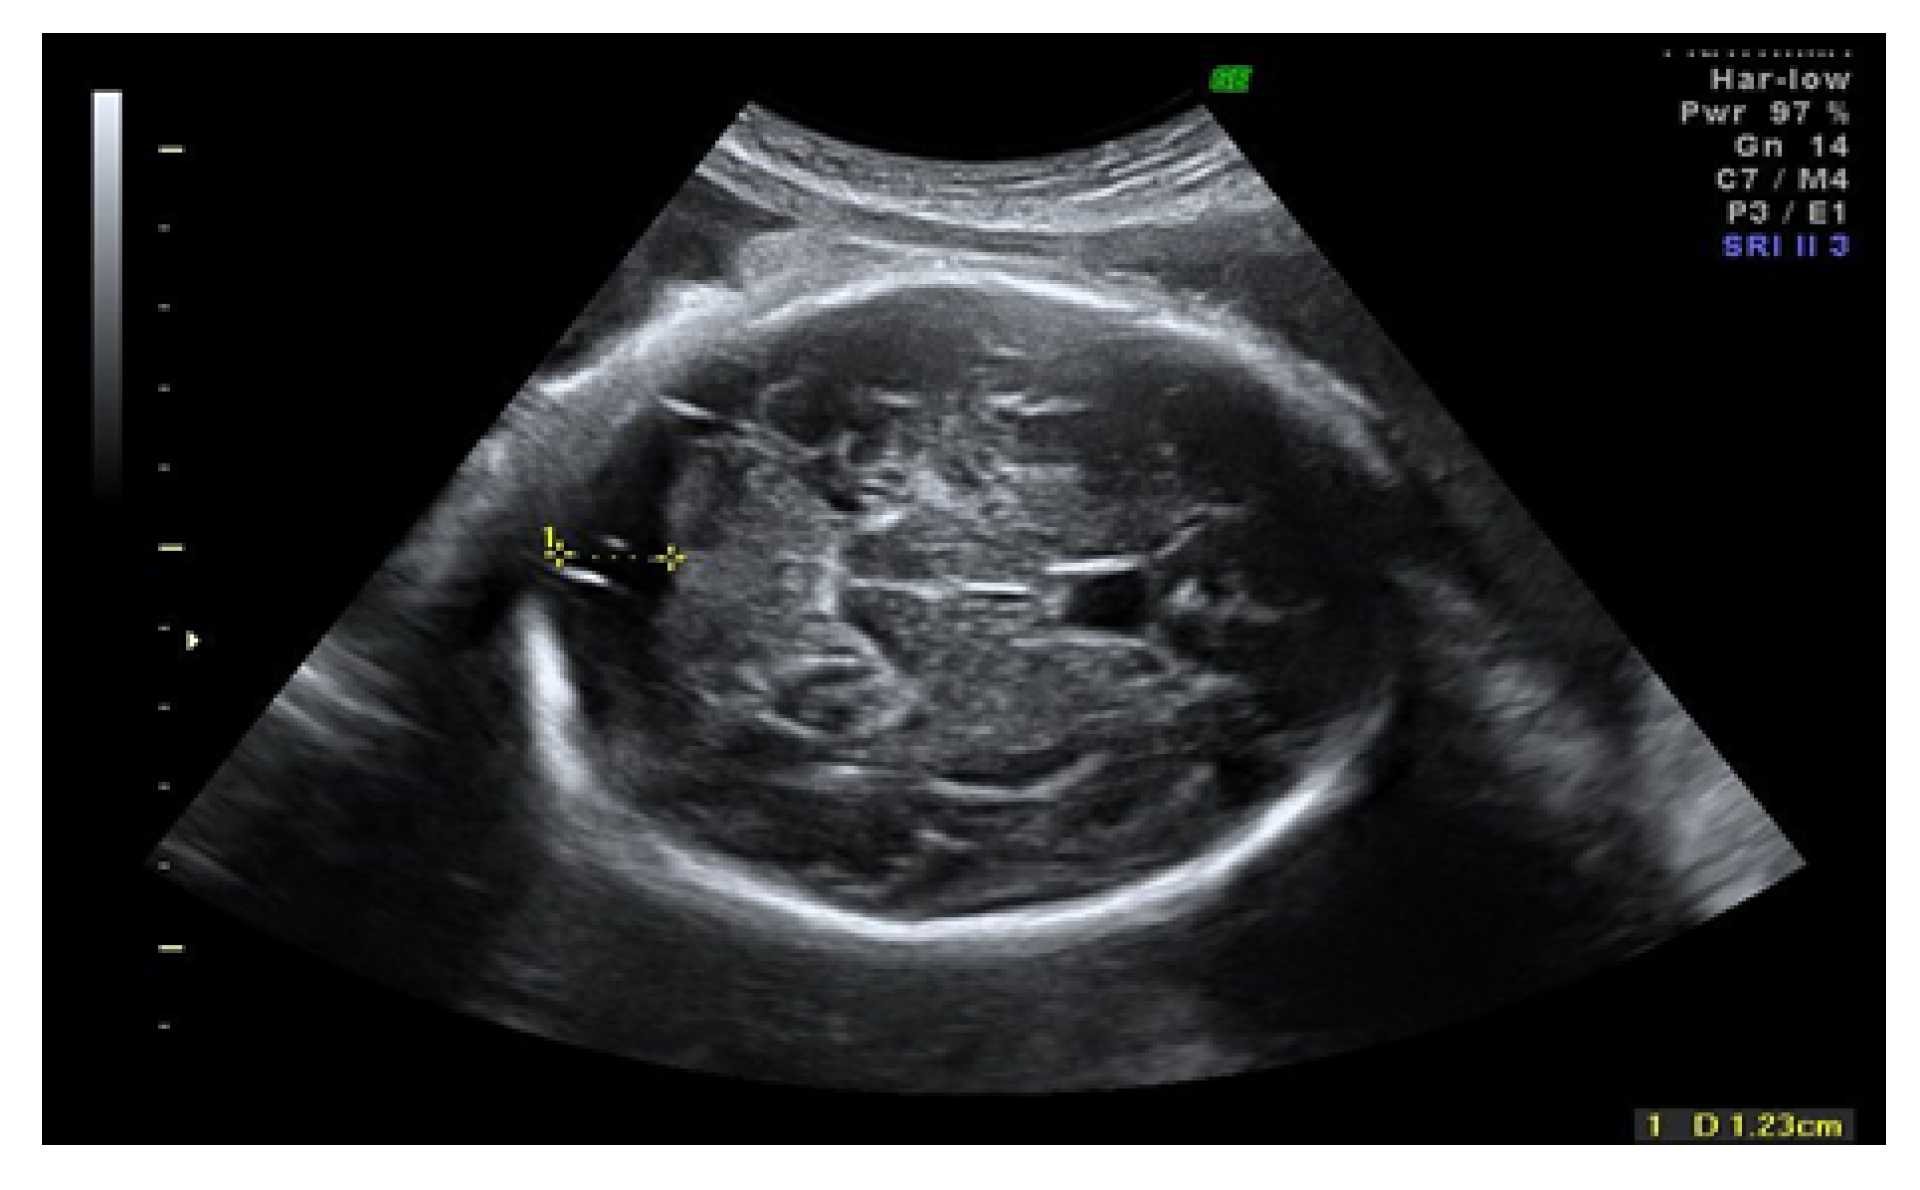

2.2. Ultrasound Imaging Technique